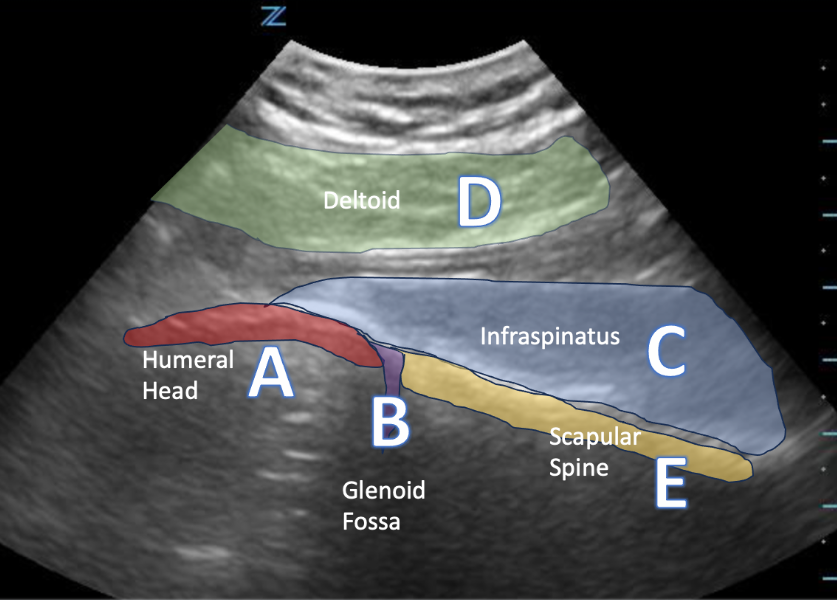

This image was captured by placing the transducer in the long axis, parallel to the scapular spine.

Image 1: Author’s own images and annotations